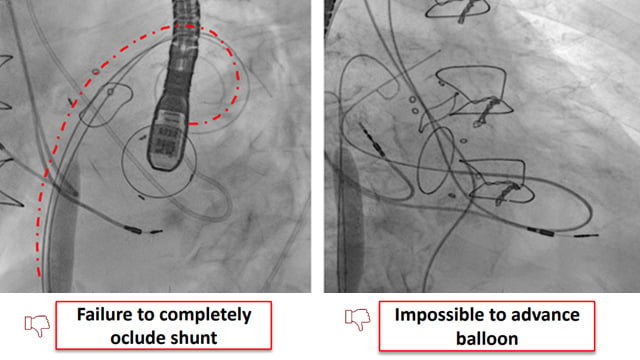

Left atrial appendage occlusion

17 Nov 2025 – From PCR London Valves 2025

This session focuses on the complexities and innovations in left atrial appendage occlusion (LAAO) procedures. It covers transesophageal ICE monitoring, challenges posed by existing atrial septal occluders, combined surgical and percutaneous approaches, and the practical experience with the Ultraseal device. These insights advance understanding of procedural...